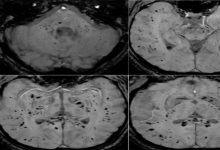

أظهرت النتائج أن حرمان النوم تسبب لفئران التجارب في اضطرابات كبيرة في ميكروبات الأمعاء: حيث انخفض عدد البكتيريا المفيدة وازدادت نسبة الكائنات الحية الدقيقة الضارة، مما أدى إلى إضعاف حاجز الأمعاء وزيادة الالتهاب في أجسام تلك الحيوانات، وساهم ذلك في دخول السموم البكتيرية إلى مجرى الدم، كما انخفضت فعالية الحماية في الدماغ، ونشطت خلايا الالتهاب العصبي، وتغير توازن الناقلات العصبية، مما أدى إلى تدهور الوظائف الإدراكية.

وبعد إضافة البوليفينول إلى النظام الغذائي للفئران، لوحظ استعادة تنوع ميكروبات الأمعاء: حيث ازداد عدد البكتيريا المفيدة من نوع “Lactobacillus” وانخفض عدد البكتيريا الضارة مثل “Desulfovibrio”، وفي نفس الوقت تعززت صحة حواجز الأمعاء والدماغ، وتراجعت الالتهابات، وعادت وظائف منطقة الحُصين–وهي منطقة رئيسية في الدماغ تشارك في تكوين الذاكرة.